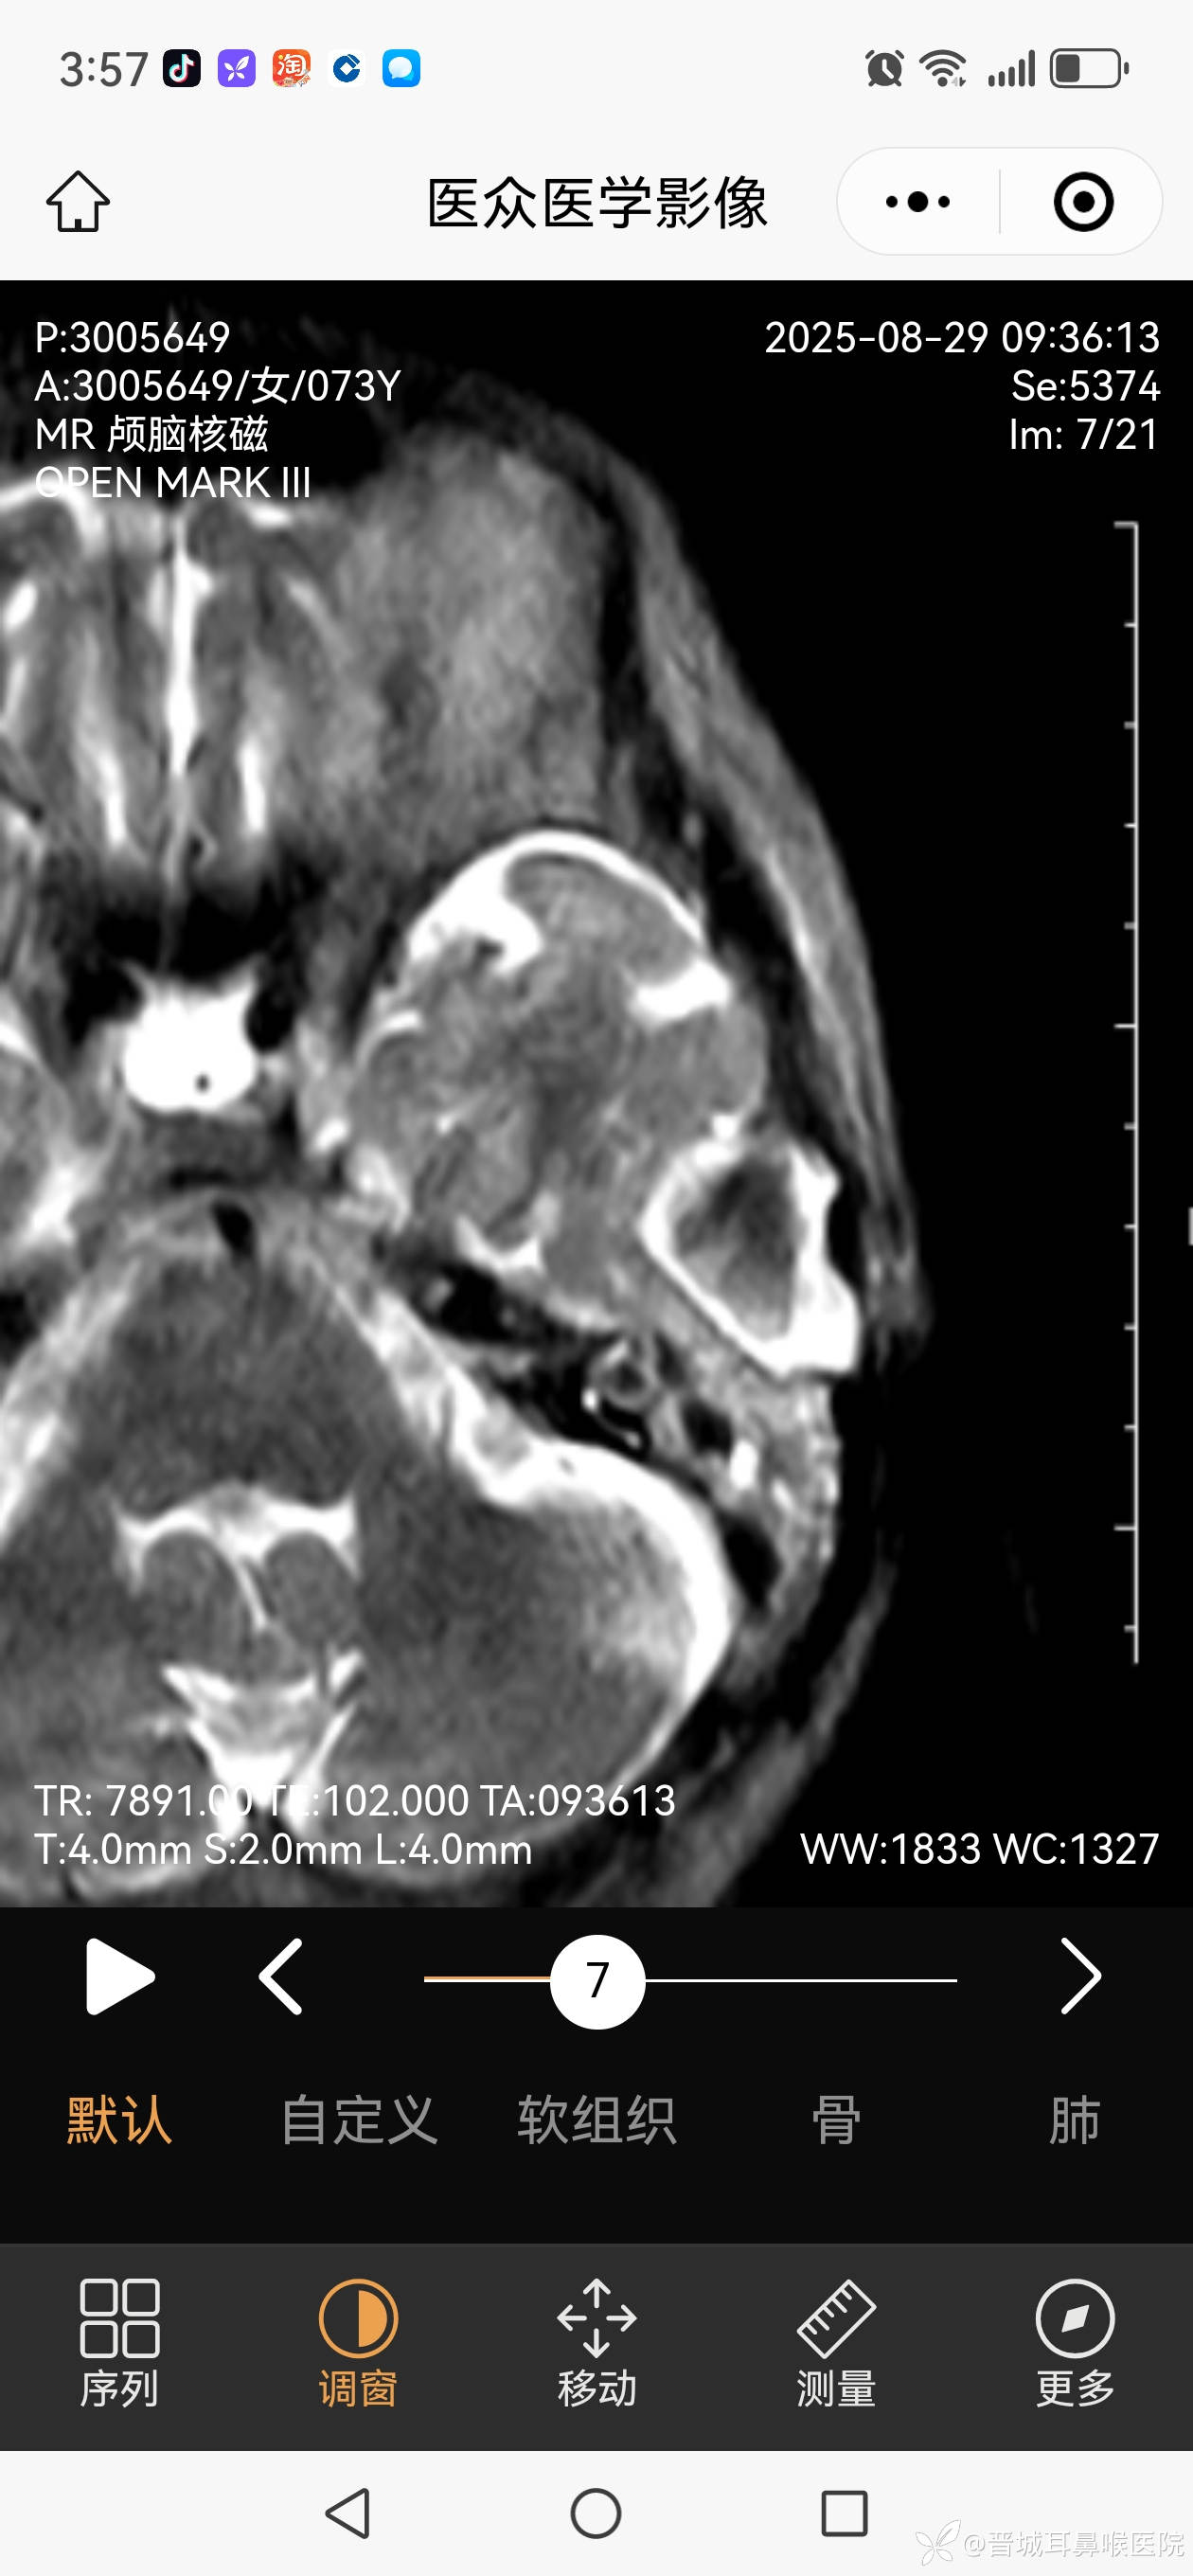

外耳道胆脂瘤不单破会后壁侵入乳突气房,更破坏前上壁,颞下颌关节囊暴露,在中颅窝形成比核桃大的胆脂瘤。